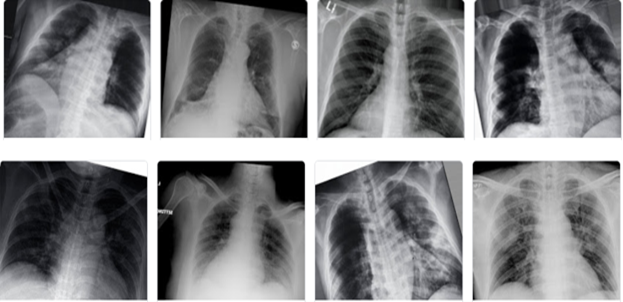

CLAHE algorithm overcomes the issue of global histogram equalization incurred due to noise amplification in homogeneous regions. It computes different histograms and utilizes them to redistribute the lightness value [15]. Primarily, CLAHE enhances the low-contrast medical images with the help of control image enhancement quality parameters, i.e., Block Size (BS) and Clip Limit (CL) [36]. CL limits the noise amplification by clipping histograms at a specified value before computing the Cumulative Distribution Function (CDF). Figure 1 and Figure 2 show non-aumgneted and augmented chest X-ray images.

Figure 1: Non-augmented chest X-ray images.